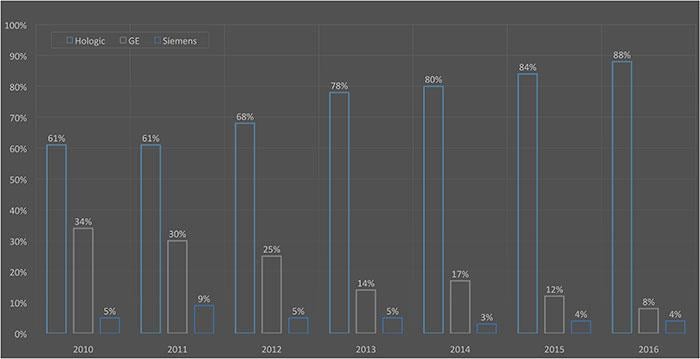

Before the introduction of 3-D digital breast tomosynthesis (DBT) imaging, 2-D full field digital mammography (FFDM) systems were the gold standard for breast cancer screening. However, during the past few years, DBT has become the new gold standard.